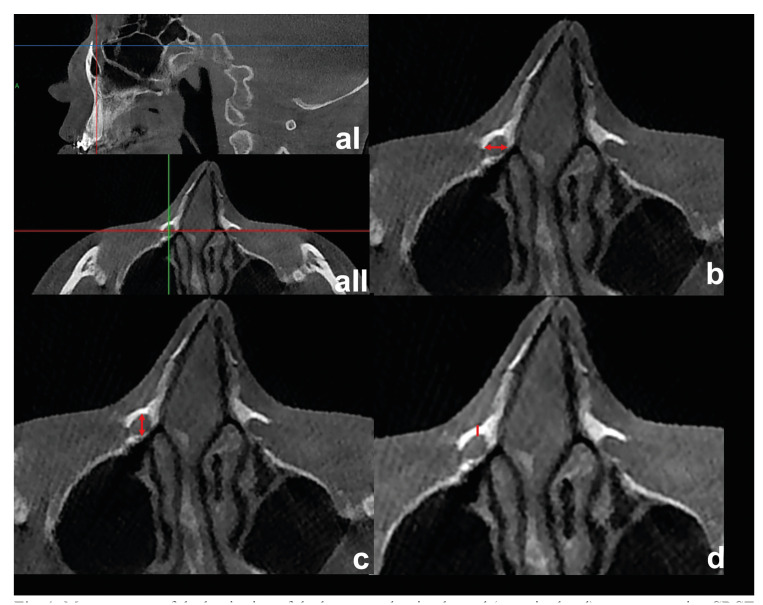

Material and methods: The authors conducted a retrospective cohort study consisting of patients who underwent Le Fort I osteotomies between 2017 and 2021 in the Erciyes University Faculty of Dentistry. The primary predictor variables were the distance of the nasolacrimal canal to the outer cortex of the maxilla and the nasal floor, as well as the superior-inferior level of the superiorly positioned screw inserted in the maxilla aperture region relative to the nasolacrimal canal. The outcome variable was the presence of a nasolacrimal duct injury. Mann Whitney U test was used for quantitative variables between the two groups. A Pearson chi-squared analysis was used to compare categorical data. A p-value <0.05 was considered statistically significant.

Results: A total of 290 nasolacrimal canals were evaluated in 145 patients, 87 females, and 58 males. The mean age was 23.47± 6.67. There was a statistically significant relationship between screw level and nasolacrimal canal perforation (p<0,001). The distance between the most anterior border of the nasolacrimal canal and the outer cortical of the maxilla was significantly less in the perforation group (p<0,001). The fixation screw was significantly closer to the nasolacrimal canal in the perforation group (p<0,001).

Conclusions: In Le Fort I surgery, nasolacrimal duct injury may occur during screw fixation to the aperture region. Superiorly positioned fixation screws in the aperture region may damage the nasolacrimal canal. In patients where the nasolacrimal canal is close to the outer cortex, care should be taken when applying the fixation screws to the aperture region to avoid damaging the canal.